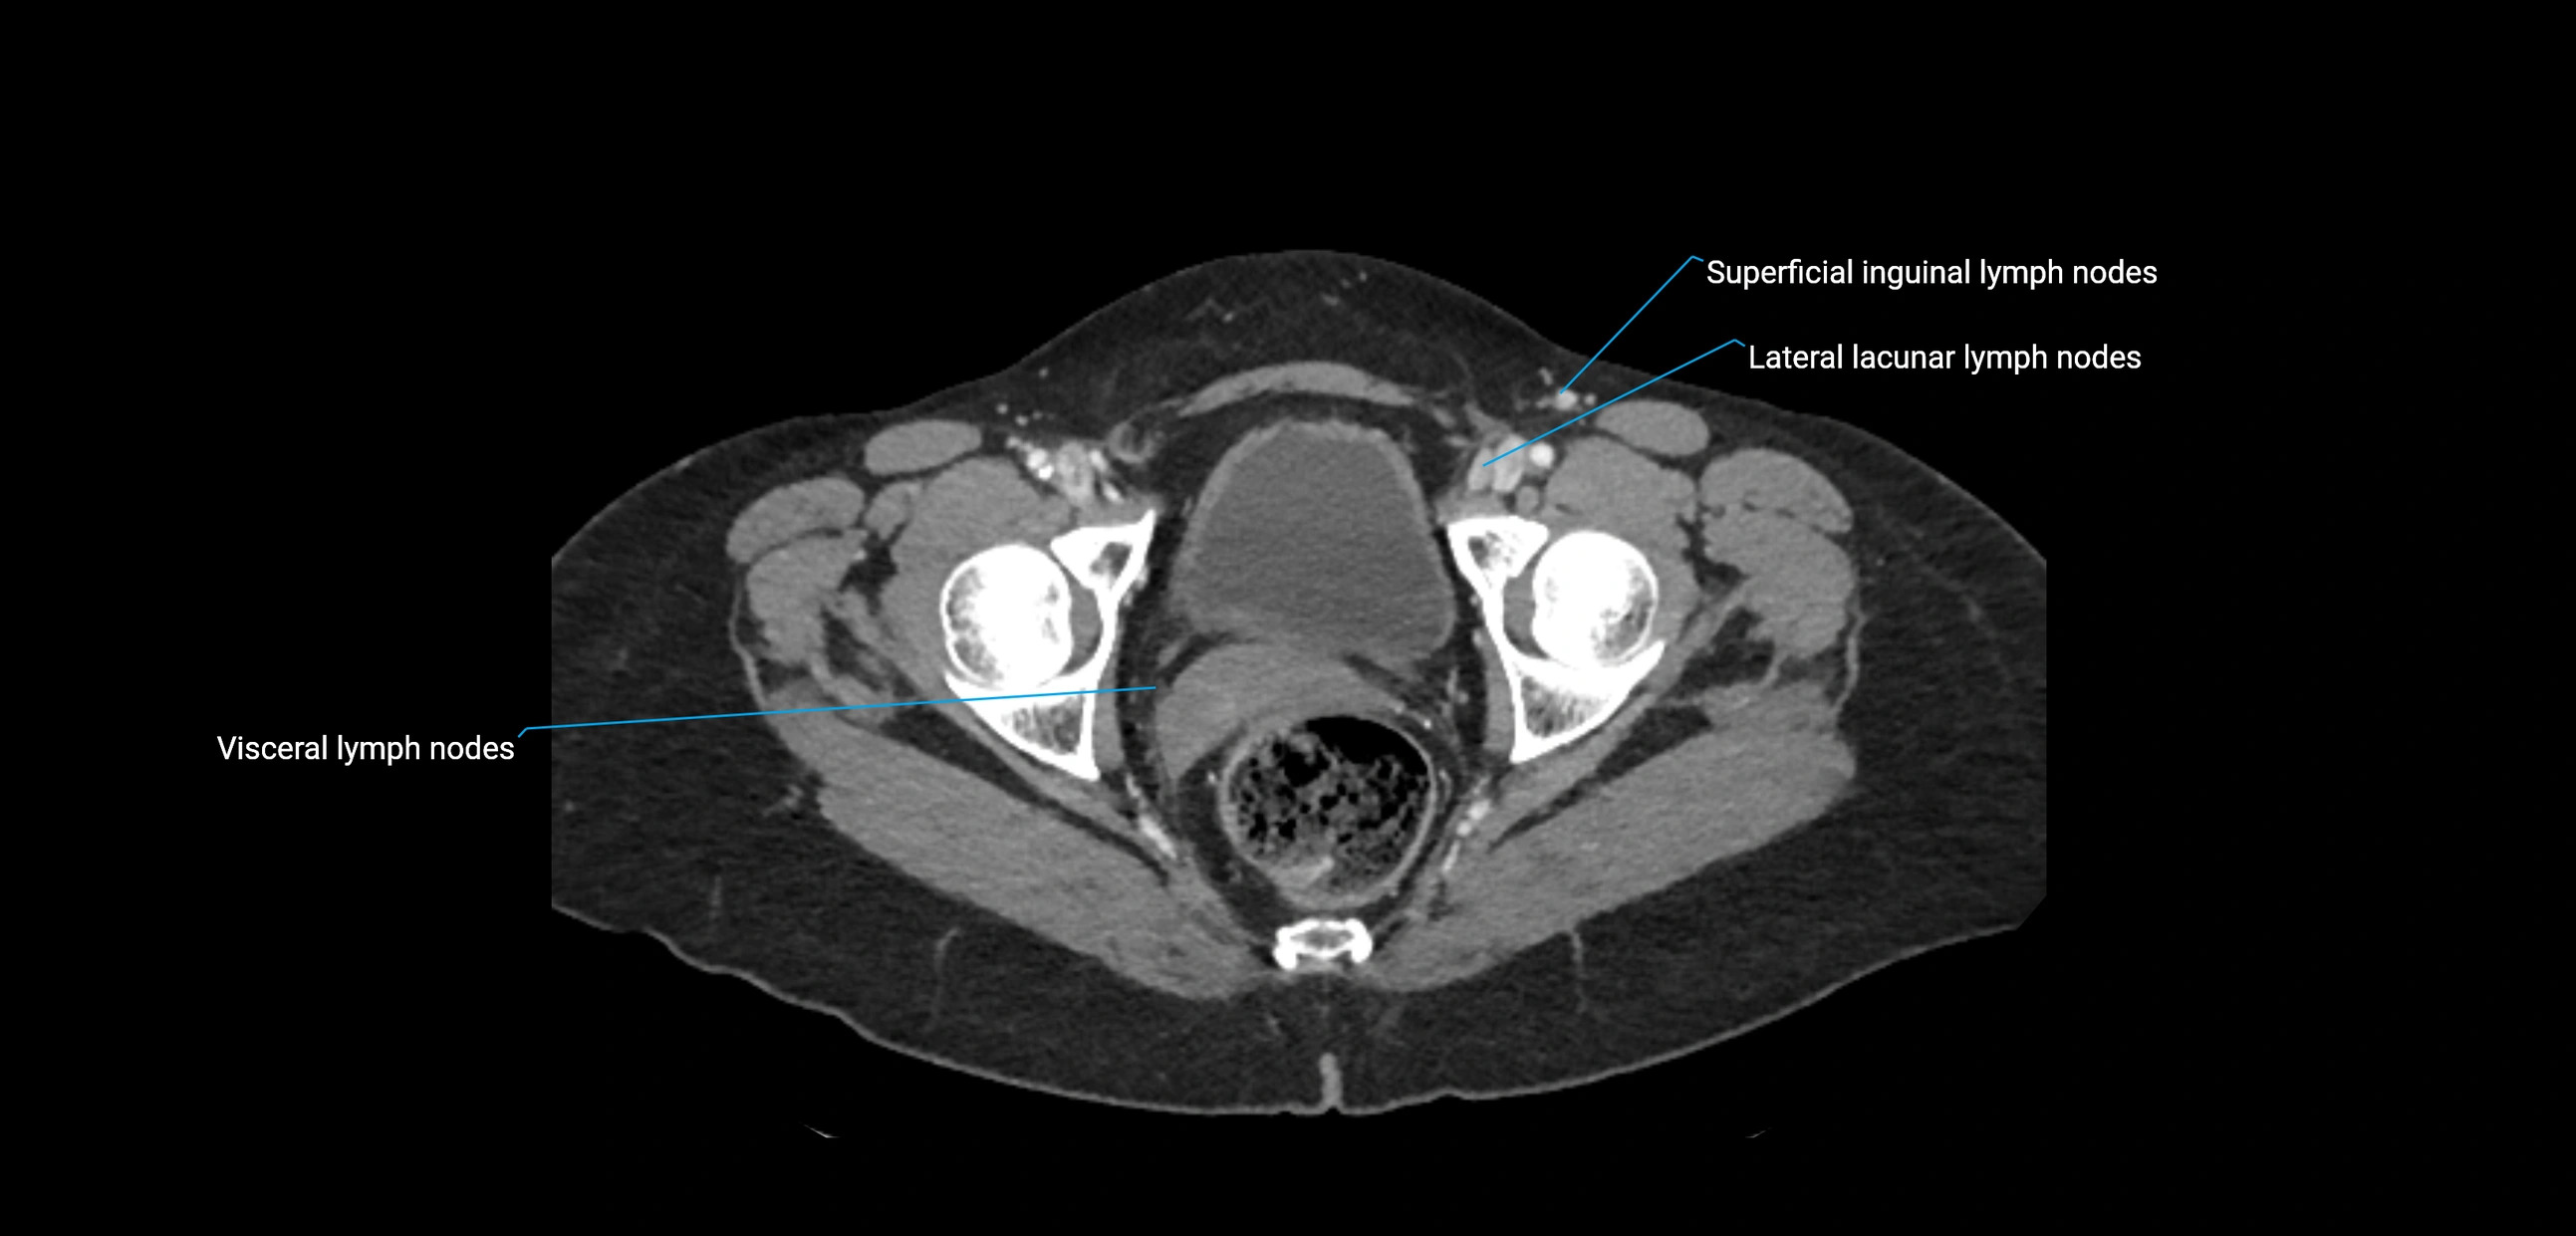

CT Appearance

CT Pre-Contrast:

• Nodes appear as soft-tissue density nodules adjacent to the aorta and IVC

• Calcification may be seen in chronic infections (e.g., tuberculosis)

CT Post-Contrast:

• Normal nodes enhance homogeneously

• Malignant nodes may show heterogeneous enhancement, central necrosis, or conglomerate formation

• Size >1 cm short axis is suspicious, though morphology and distribution are equally important